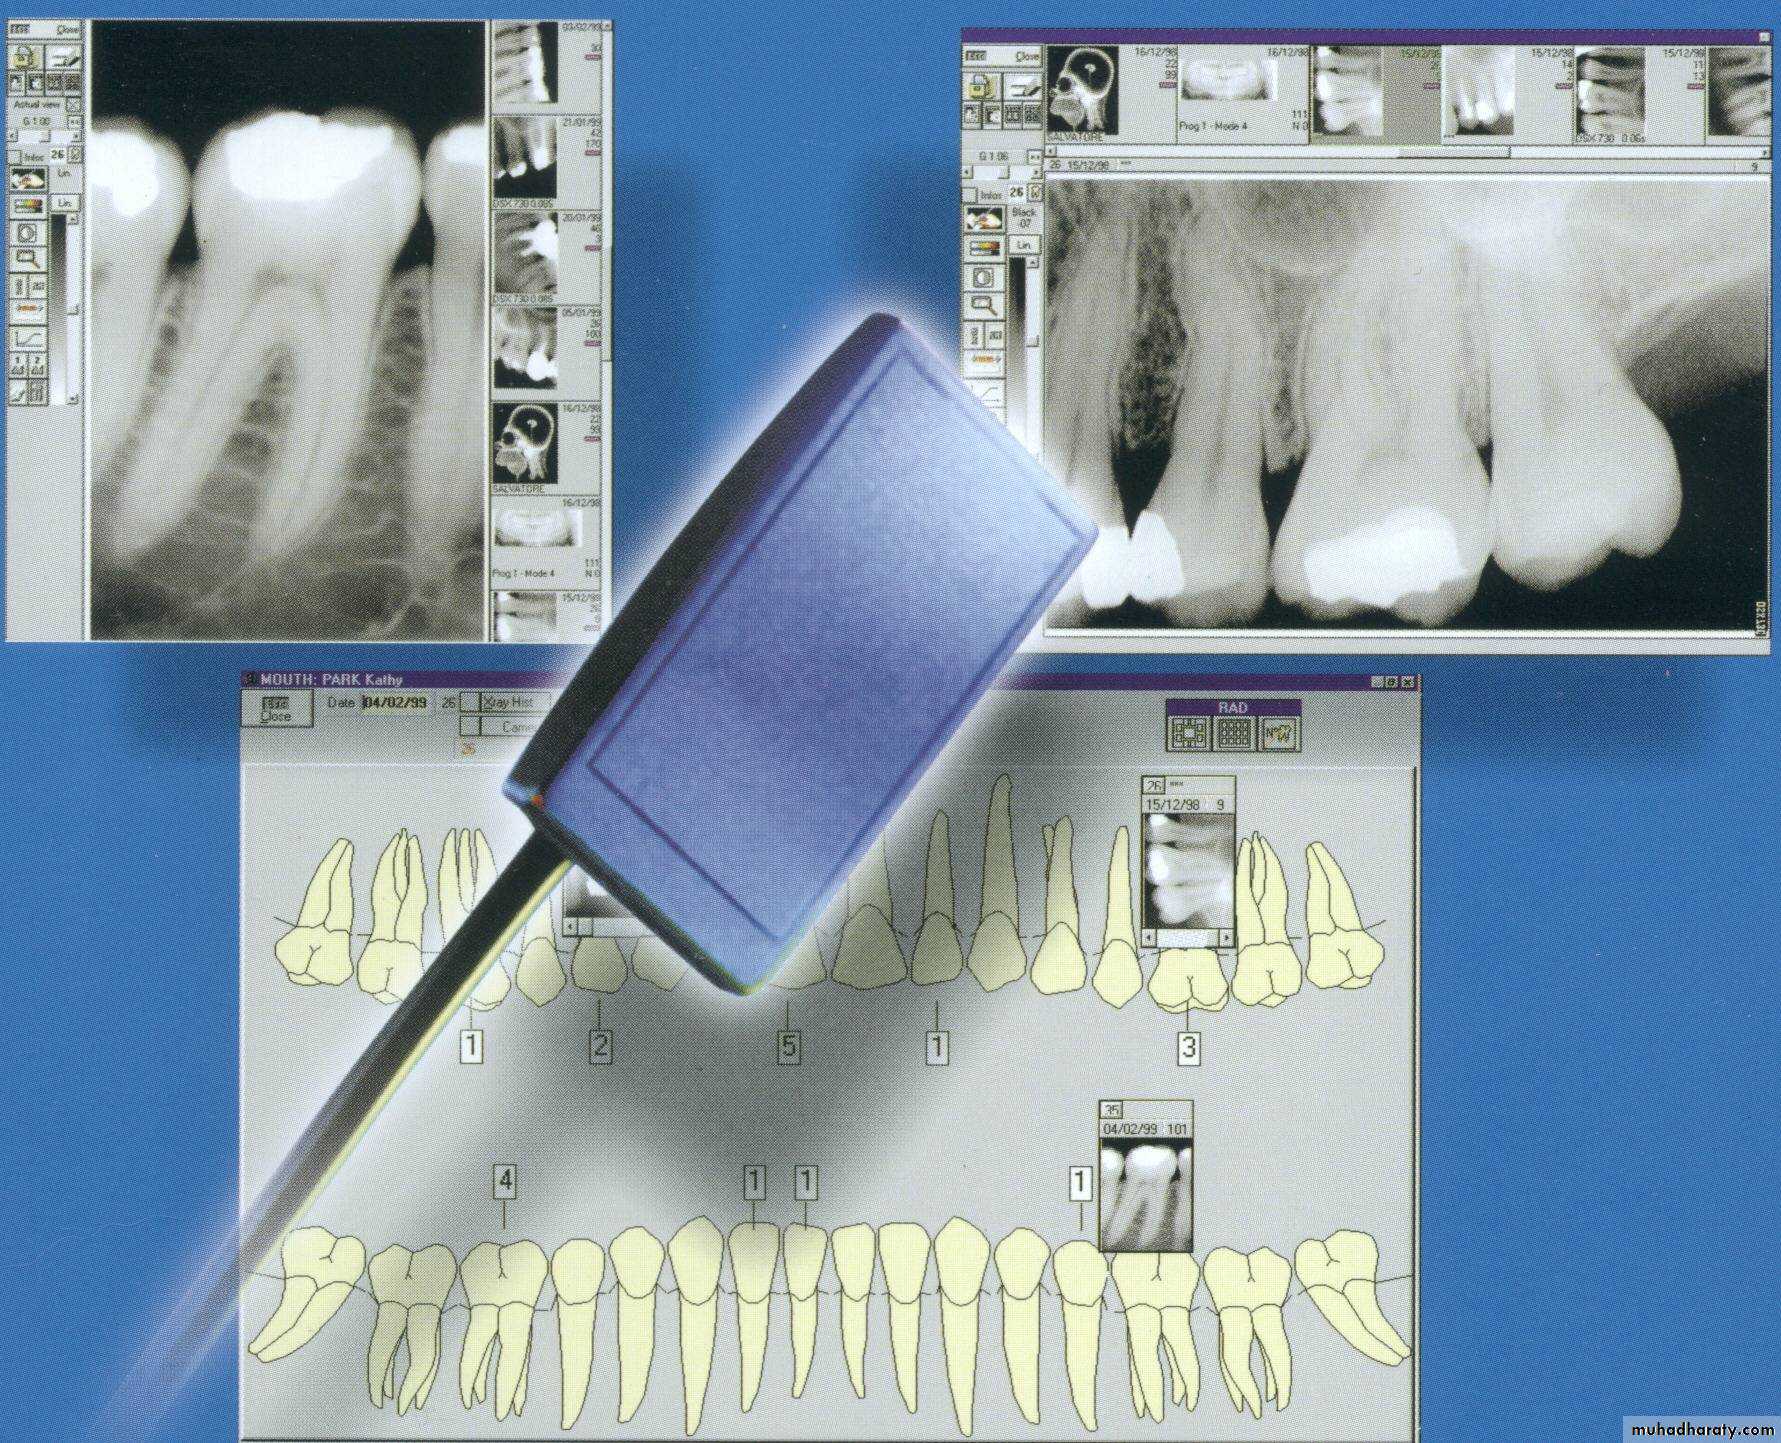

Advanced Radio.-Digital radiography

-Image recorded with non film receptor

The film replaced by flat electronic pad or sensor

-Images sent to computer displayed on monitor screen